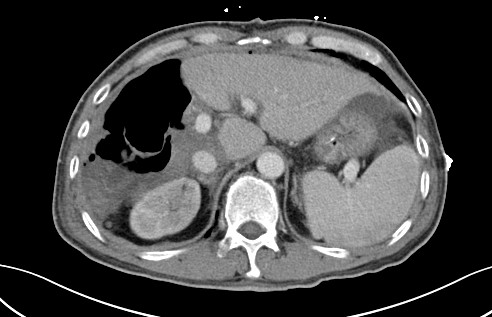

二次手術完整切除腫瘤

于是,專家團隊便于10月中旬為患者實施了第二階段腫瘤切除術,在此過程中,由于患者同時合并腹繭癥,通過第一次手術的刺激腹腔內粘連非常嚴重,手術遭遇了巨大的困難,最后經過近7小時左右的艱苦奮戰(zhàn),攻堅克難,終于完整切除了患者右肝的巨大腫瘤,手術取得了成功,患者重獲新生。

術后,患者經過10多天的恢復治療,順利康復出院。出院后,經科室多次電話回訪,現患者身體狀況和生活質量良好。